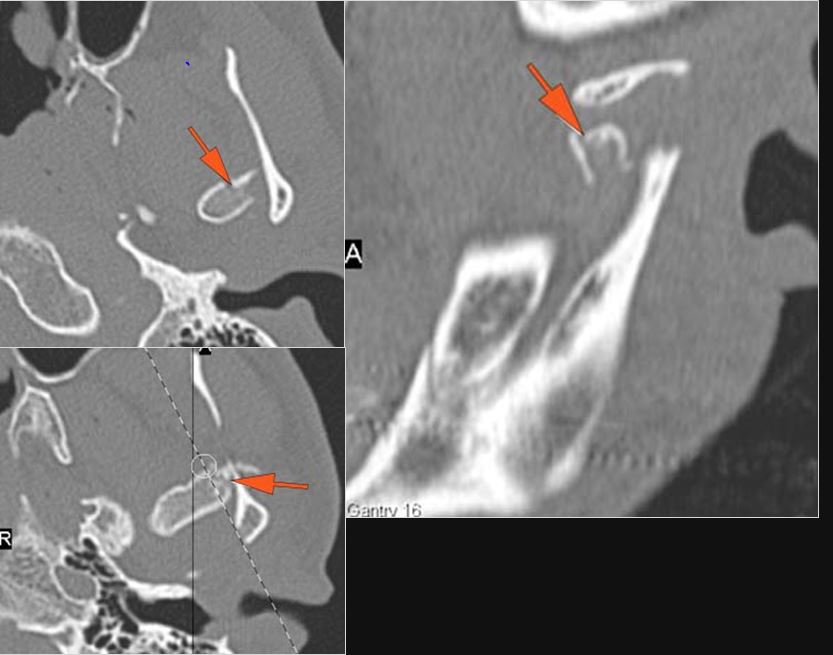

The condylar head and fossa as well as the temporomandibular joint space are abnormal.

There is condylar fracture either within or outside of the joint capsule, or with or without involvement of the articular surface of the condylar head.

There is bony injury or displacement of the external auditory canal and/or other evidence of temporal bone injury.